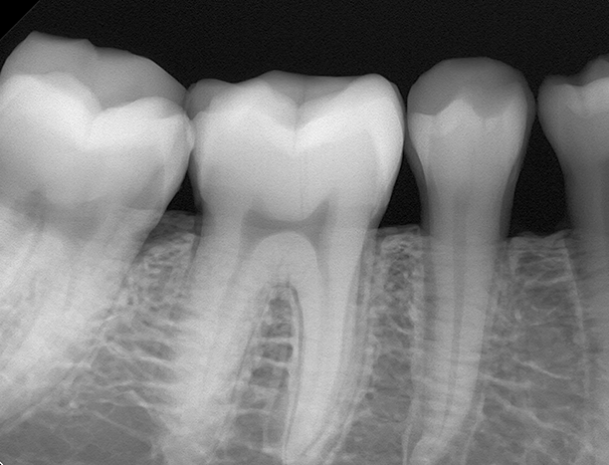

Offering high performance imaging from lower radiation doses than film and built on more than twenty years’ experience in the design and manufacture of image sensors, our x-ray dental image sensors have helped transform the way in which x-ray images are captured, stored and retrieved in dental offices.

We work closely with customers to develop customised dental imaging sensors to suit individual requirements.